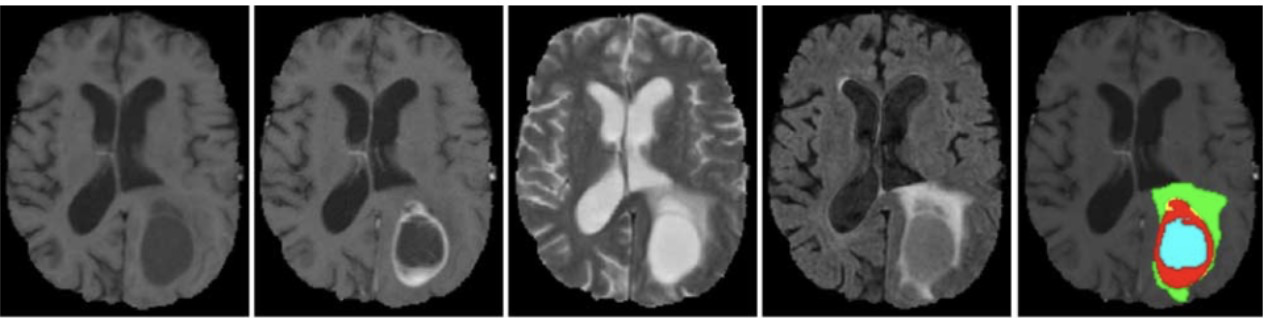

Deep Learning With Magnetic Resonance And Computed Tomography